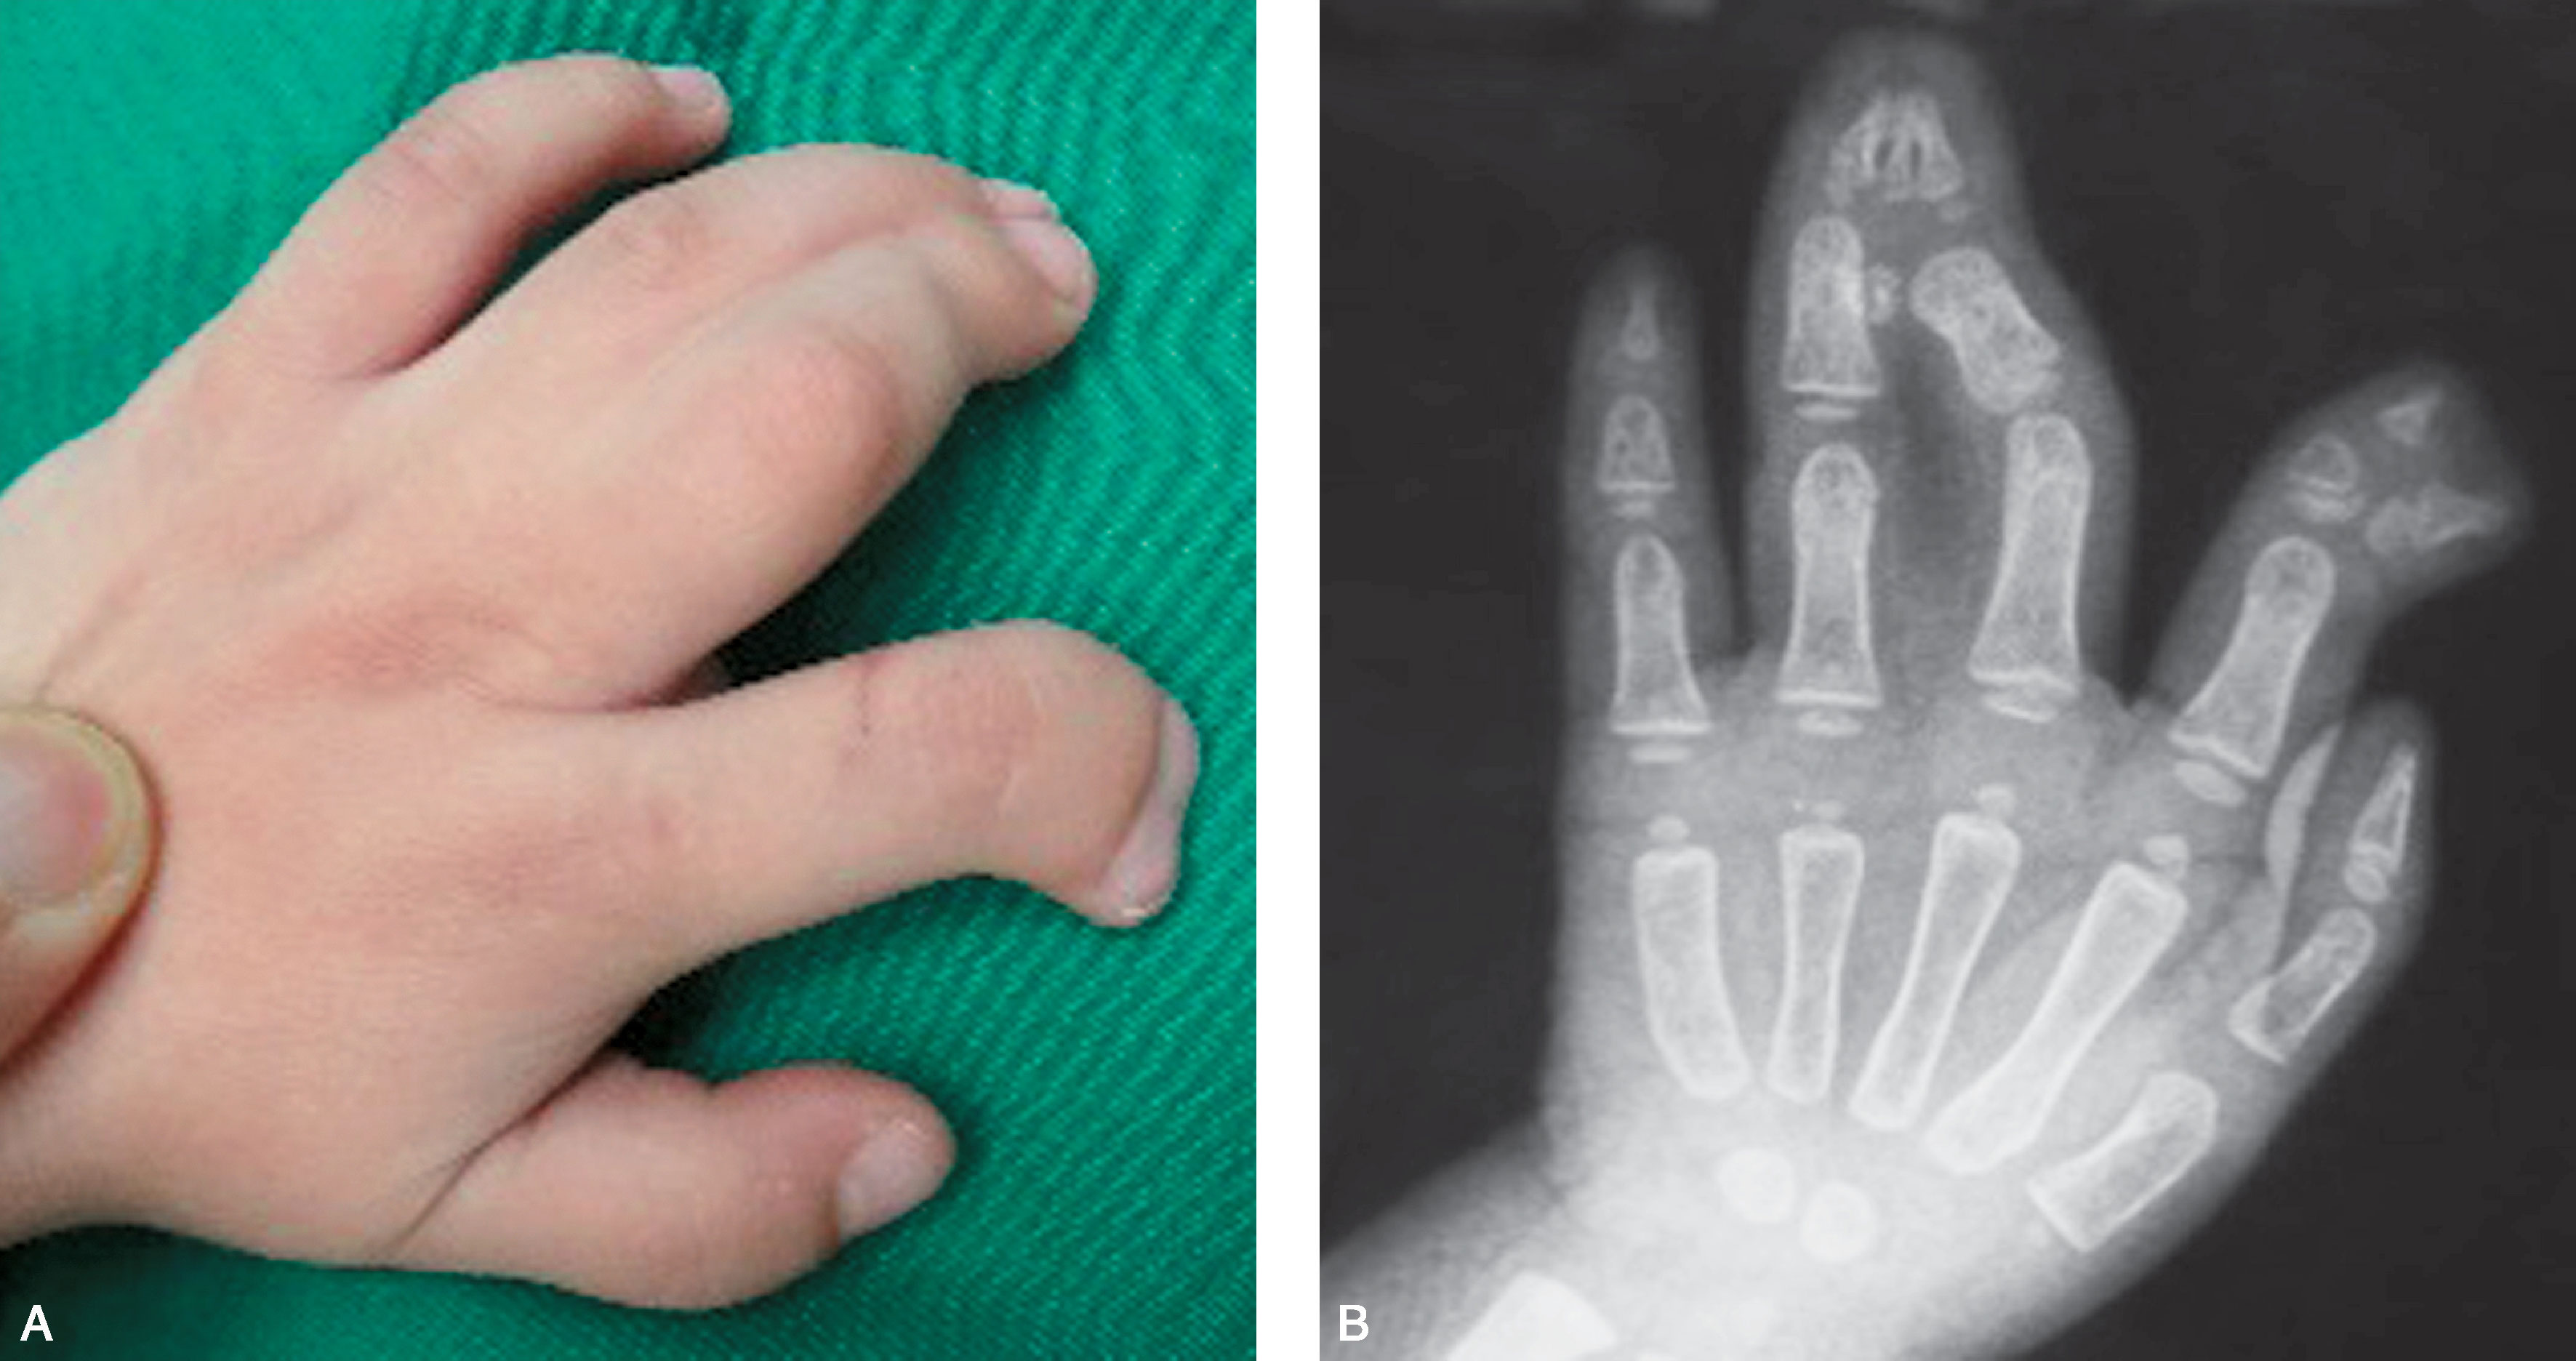

图2-3-7 掌骨水平中央型多指

A.右示指多指,外形完整;B.X 线片显示示指多指位于掌骨基底,掌骨完全分离,多指骨关节结构发育好,选择切除桡侧示指,术中需设计重建拇指蹼及重建拇内收肌功能,也可切除尺侧示指,同时将桡侧示指在掌骨基底水平移位于尺侧示指,与前者不同的是不需要重建拇指蹼及重建拇内收肌功能,但需修复示中指掌骨头间横韧带及重建示、中指指蹼